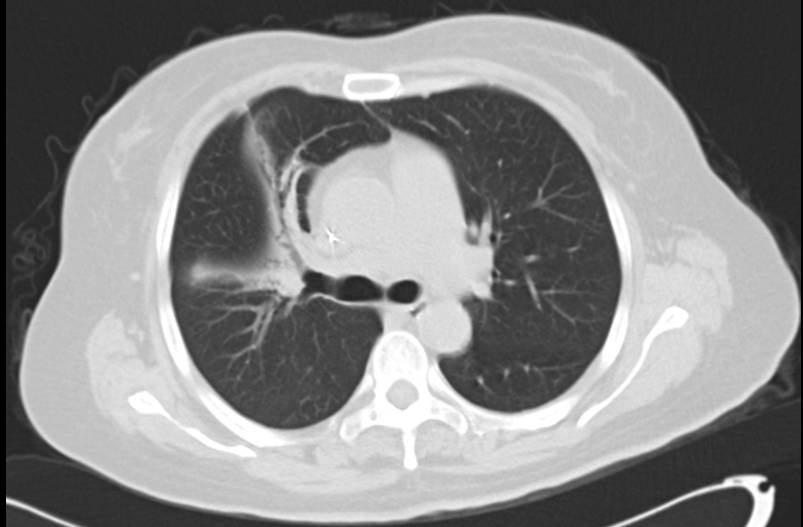

患者女性,50岁.因右侧胸痛1年余,加重伴间断发热10天入院。无咳嗽咳痰,无咯血,无胸闷憋气。查体:右侧语颤增强,右肺叩诊呈实音,可闻及干湿性罗音.既往有宫颈囊肿、中度贫血。肺CT示右肺大片密实影(图1),内有支气管充气征,院外诊断为肺炎,反复应用多种抗生素无效,拟诊“肺炎,浸润性肺腺癌?”收治入院。

图1 肺CT:右肺上叶见大片高密度影,内含支气管征,气管、支气管通畅。纵膈内未见明显肿大淋巴结。